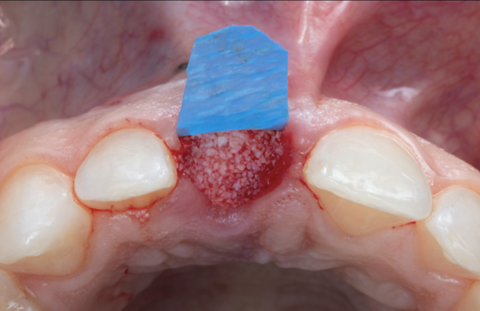

Indication: multiple recession sites and a thin phenotype – for improved root coverage and long-term tissue stability. A case report by Nicolas Garros.

Nicolas Garros